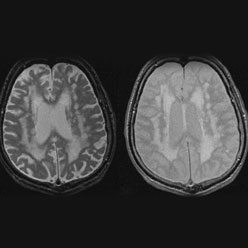

Cryptogenic (“of mysterious cause”) ischemic strokes comprise about 25% of all ischemic strokes in recent studies.  There is strong evidence that most cryptogenic strokes are embolic, with the thrombus originating from any of several well-established potential embolic sources, including minor-risk or covert cardiac sources, veins via paradoxical embolism, and non-occlusive atherosclerotic plaques in the aortic arch, cervical or cerebral arteries.  The novel pragmatic construct of “embolic strokes of undetermined source” has been proposed since an embolic mechanism is likely, but the embolic source is uncertain.  Because emboli consist mainly of thrombus, it is hypothesized that anticoagulants will reduce recurrent brain ischemia more effectively than antiplatelet agents.

We initially carried-out a global survey consecutive patients with acute ischemic stroke to define the fraction who have ESUS and their features (Perera KS et al Embolic strokes of undetermined source: Prevalence and patient features in the ESUS Global Registry. International J Stroke 2016; 11: 526-33).  This project,informed the study design of a randomized trial testing direct-acting oral anticoagulants for secondary prevention in ESUS patients.  The global trial (NAVIGATE ESUS (Clinicaltrials.gov.NCT02313909)) began enrolling patients in December 2014 and is sponsored by Bayer AG, with C-SPIN sponsorship of a biomarker/genetics sub study.